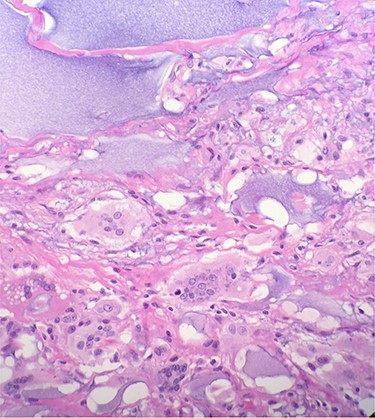

Gross pathologic examination of breast specimens demonstrated presence of pink-tan colored membranous tissue, consistent with fibrotic capsular tissue intermixed with polymers of polyacrylamide. Microscopic examination demonstrated presence of benign breast tissue with fibrosis, foreign body giant cells and chronic inflammatory cells. There was extensive purple, gelatin-like material which represented the presence of polyacrylamide hydrogel (Fig. 3).

Microscopic examination reveals benign breast tissue with fibrosis, foreign body giant cells and chronic inflammatory cells (H&E 20×) Extensive, scattered, purple, gelatin-like material was also present which represents the presence of polyacrylamide hydrogel.